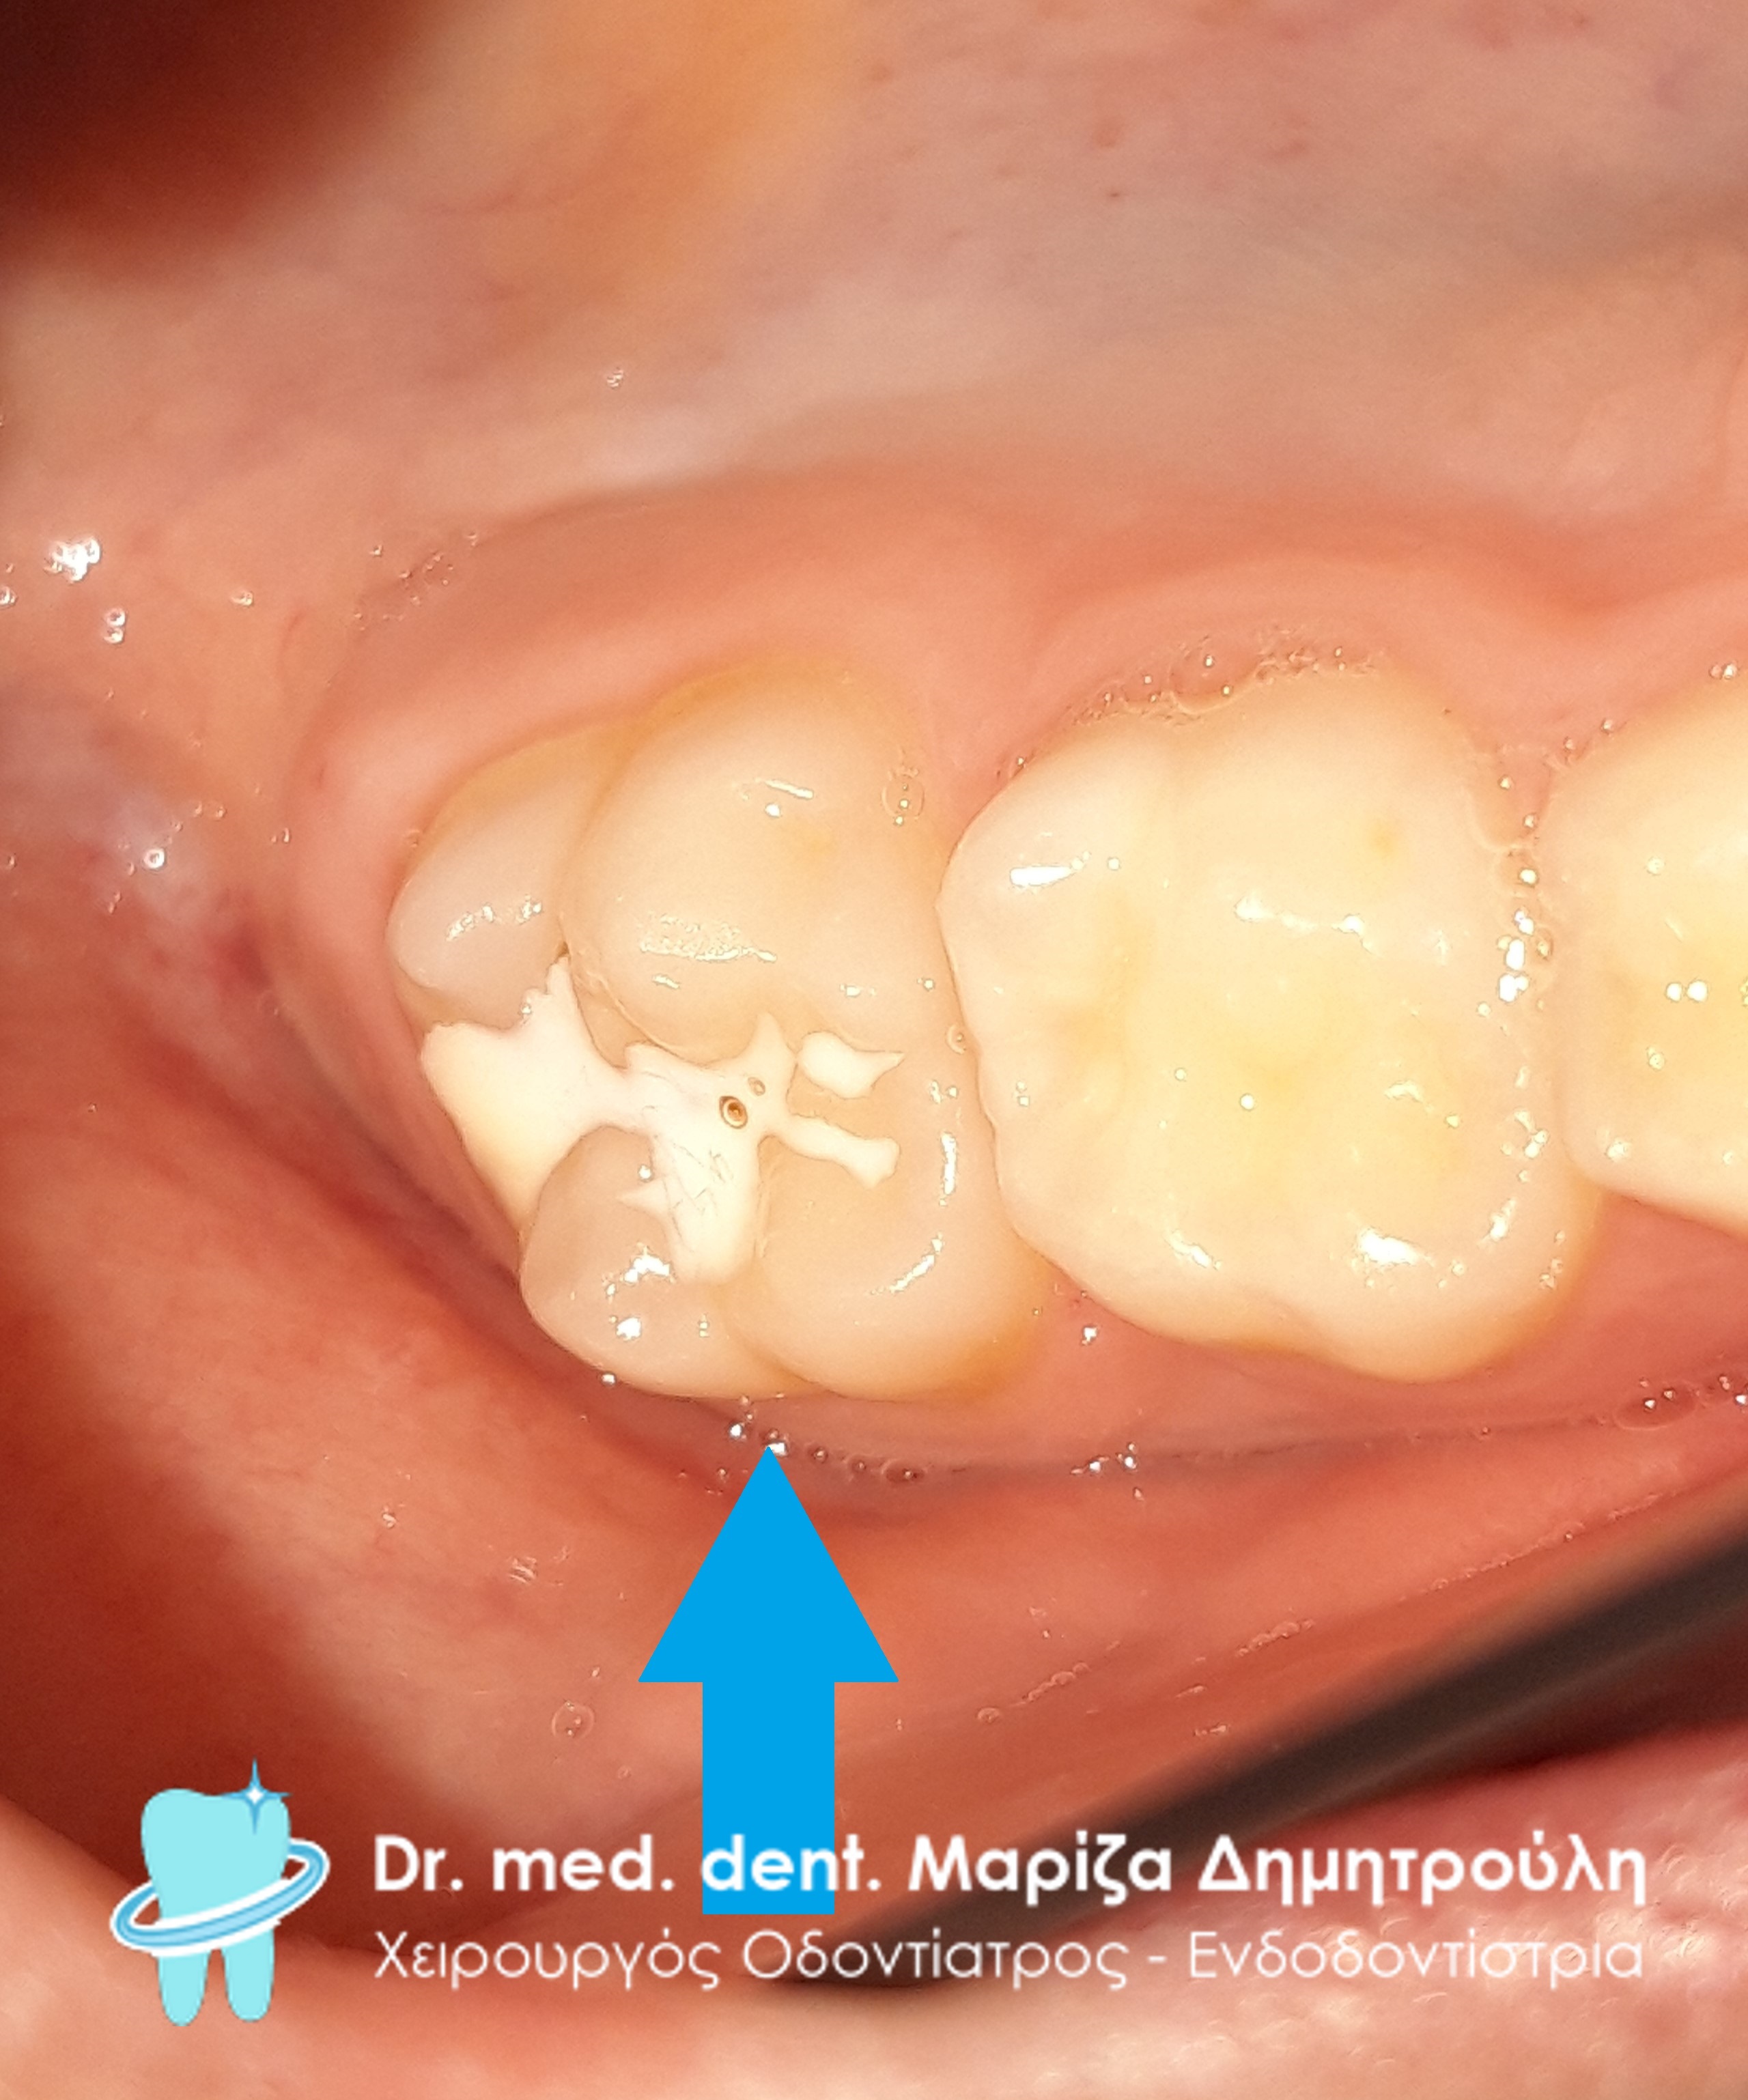

Στα πλαίσια του τυπικού οδοντιατρικού ελέγχου διαπιστώθηκε η ύπαρξη μιας μικρής τερηδονικής κοιλότητας στον πρώτο αριστερό μόνιμο γομφίο. Αποφασίστηκε η αφαίρεση της επιφανειακής αρχόμενης τερηδόνας και προληπτική κάλυψη οπών και σχισμών (sealant) στη μασητική επιφάνεια του μόνιμου άνω αριστερού πρώτου γομφίου.

Στο συγκεκριμένο ασθενή πραγματοποιήθηκε ταυτόχρονα αφαίρεση της επιφανειακής αρχόμενης τερηδόνας και προληπτική κάλυψη οπών και σχισμών (sealant) στη μασητική επιφάνεια του άνω αριστερού πρώτου γομφίου.